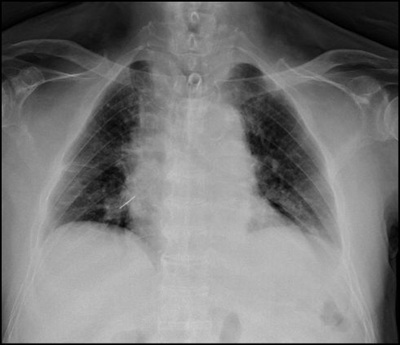

서울대병원은 29일 기자회견을 갖고 "노태우 전 대통령의 흉부 우측 주기관지를 관통하고 있던 금속성 이물질(침)을 28일 전신마취를 통해 제거했다"며 언론에 사진을 공개했다.

이날 공개된 X-ray 사진에는 7㎝ 길이의 금속 침이 노태우 전 대통령의 가슴 오른쪽 폐 속으로 연결된 양쪽 조직을 관통하고 있다. 노 전 대통령은 지난 27일 오후 2시경 오른쪽 폐에서 침이 발견돼 제거 수술을 받기 위해 입원한 것으로 알려졌다.

서울대병원측은 4월 28일 오전 전신마취 하에 내시경을 이용해 성공적으로 침을 제거했다.

| <노태우 전 대통령 엑스레이 사진> |